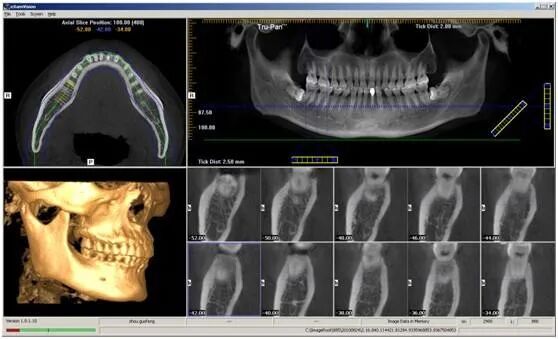

CT相对其他牙片来讲,不管是功能还是设备上都是比较高级的,在一般门诊或医院无法拍摄,只有专门口腔医院里才能见到。

牙科

CT

主要用于植牙前对牙槽骨

(

上、下颌骨包围和支持牙根的部分

)

高度、宽度、神经管的位置、植入种植体的长度等准确诊断。

检查提高了牙科手术的准确性,更重要的是可在电脑上进行模拟种植,使颌骨阻生牙和埋伏牙可以在拔除前确定手术切口方向,减少盲目性,避免损伤下颌神经。

在根管治疗时,也可以确定根管数目和根尖病变范围、有否根折及根冠钙化等情况,为准确寻找根管及治疗结果的预测提供参考。